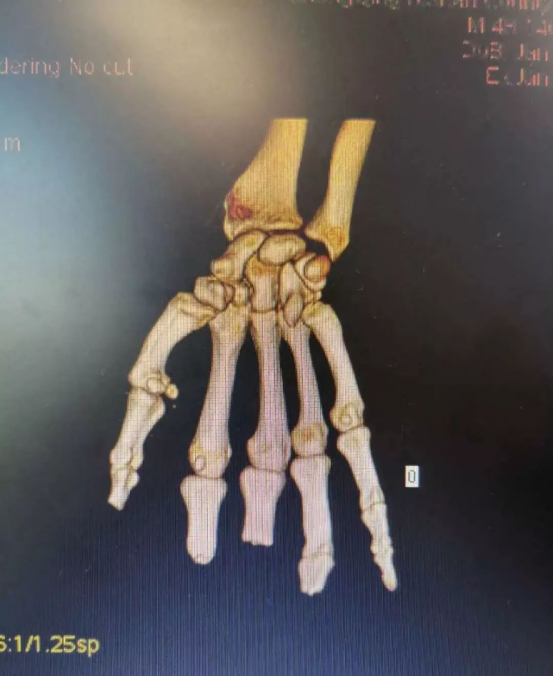

在放射科的支持下,醫(yī)院對患者雙手進行了CT三維重建,通過技術處理,虛擬出了患者缺失的手指,再使用新型材料打印出3D模型,模擬患者的斷指。通過對3D模型進行設計取樣,對患者右拇指、中指精準再造。